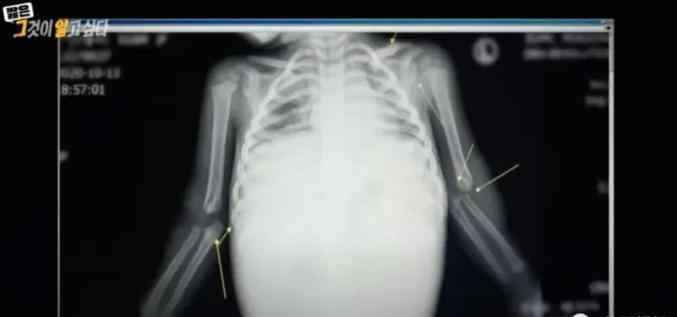

医生抢救时,对郑仁的身体状况感到非常震惊。一个快2岁的孩子,体重只有8.5公斤。身上到处是瘀伤,胳膊、锁骨、腿部都骨折了。

更可怕的是,这么小的孩子胃部居然充满了积血,内脏严重破裂,就连胰腺都完全破了。

胰腺位于身体的后部。前面还有胃、腹壁和结肠等器官保护,很难受到如此严重的伤害。除非是交通事故等猛烈冲撞。

医生顿时萌生了恐怖的猜测,除非是一个成年人从沙发上跳下去,狠狠踩在孩子身上,才有可能让郑仁的胰脏破裂。

▲ 孩子身上的受伤部位示意图

负责急诊的医生指向郑仁去世前的X光片说:“这是足以被印在医学教科书中的儿童虐待情况。”